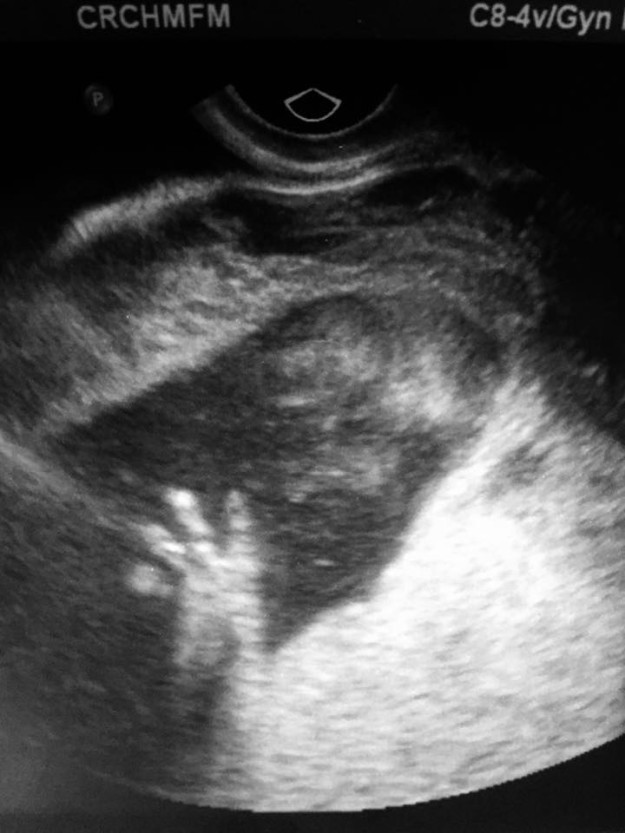

In February 2016, Paradiso was 18 weeks pregnant with her daughter Omara when doctors discovered a mass on the baby’s neck during a routine ultrasound.

The ultrasound showed a bubble on Omara’s neck, which she said doctors believed was a rare tumor called a “teratoma” but wouldn’t know more until they did an MRI.